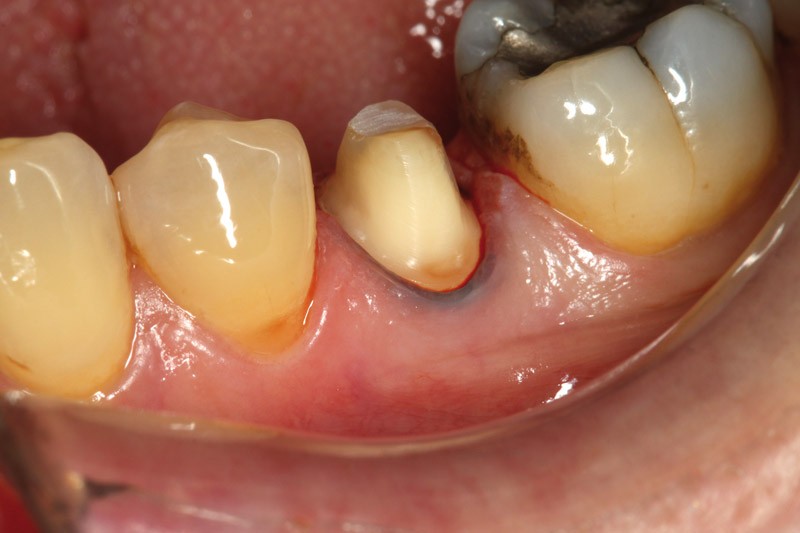

Voici un exemple clinique de mise en œuvre dans le cadre de la réalisation d’une couronne sur une 35, en un seul rendez-vous.

La préparation corono-périphérique est réalisée avec une limite cervicale juxta-gingivale ou légèrement intra-sulculaire, un fil de soie noir est placé dans le sulcus pour améliorer la lisibilité de la limite cervicale.